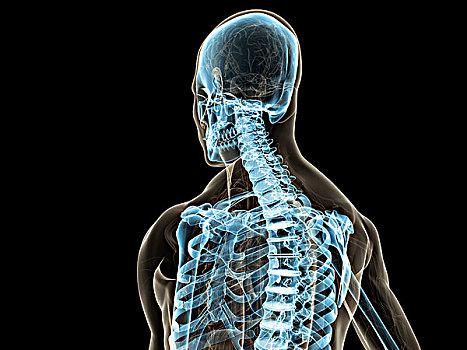

为什么肺癌会“折腾”我们的喉咙?它和解剖结构有关从解剖学角度来说,肺部和喉咙虽然分属不同系统,但它们之间通过喉返神经这条“线路”紧密相连。

右肺癌如果长在靠近肺门的位置,或者左肺癌靠近主动脉弓区域,就有可能压迫喉返神经。

一旦神经被压迫,就会出现声音嘶哑、咽部异物感、吞咽困难等症状。

这种“远程影响”是肺癌的一个典型特征。

还有一种情况是,肺部的肿瘤形成转移,尤其是淋巴转移,也可能影响颈部和咽喉部位的神经组织。

这也解释了为什么一些看似“嗓子有问题”的人,实质问题却藏在胸腔深处。